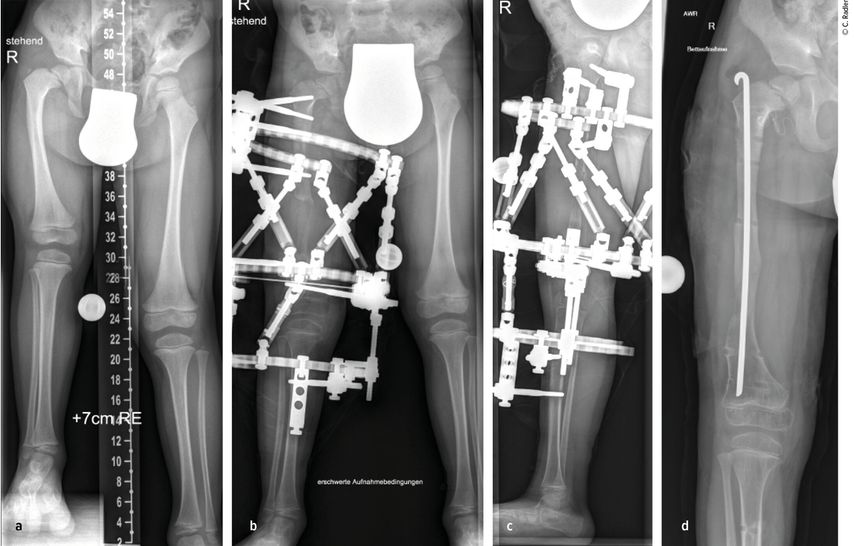

Pathologie am Kniegelenk

Sowohl beim CFD wie auch bei der FH zeigen sich deutliche Pathologien am Kniegelenk. Es besteht eine Hypoplasie der lateralen Epiphyse mit entsprechenden Wachstumsstörungen, was zu einem rezidivierenden Valgus am Kniegelenk führt.3,4 Zusätzlich besteht in vielen Fällen eine deutliche Instabilität des Kniegelenkes. Es findet sich eine Hypoplasie des ACL in etwa 15% und ein vollständiges Fehlen des ACL in etwa 85% der Fälle.5 Das PCL ist in etwa 21% hypoplastisch und in etwa 24% ebenso fehlend. Diese Instabilität des Kniegelenkes ist bei milden Formen oft klinisch im Alltag nicht relevant, kann jedoch während einer Verlängerung zu massiven Problemen im Sinne von Luxation und Subluxation führen. Zusätzlich zeigt sich oft eine Lateralisation der Patella, wobei diese auch permanent luxiert lateral am Femurkondyl liegen kann.

Die Valgusstellung kann sehr einfach über eine Wachstumslenkung (Hemiepiphysiodese mit 2-Loch-Platte) korrigiert werden. Um eine Subluxation am Kniegelenk zu verhindern, muss bei allen diesen Fällen bei Verlängerung mit Fixateur dieser knieüberbrückend montiert werden (Abb.4). Bei Verlängerung über einen Verlängerungsmarknagel wird in diesen Fällen eine Oberunterschenkelschiene (KAFO) verwendet und prophylaktisch, soweit noch vorhanden, die Fascia lata auf Höhe des oberen Patellapols durchtrennt. Bei deutlicher Instabilität oder auch Subluxation ist eine Stabilisierung über eine komplexe Operation, die als Super-Knee-Operation subsumiert wird, erforderlich.2 Diese Operation kann auch an die Hüftrekonstruktion/Super-Hip-Operation angeschlossen werden, da hier die Faszie ohnehin präpariert wird. Je nach Alter des Patienten und dem Ausmaß der Instabilität wird hierbei die Fascia lata nach Präparation bis an das Tuberculum Gerdyi und Halbieren der Länge nach entweder extraartikulär oder intraartikulär geführt. Auch die Fixation wird abhängig vom Alter mit Biotenodeseschrauben oder Weichteilzügelung durchgeführt.

Abb. 4: Platzierung (a–d) eines Fixateur externe mit Knie-Überbau (e–g) zum Schutz vor (Sub-)Luxation